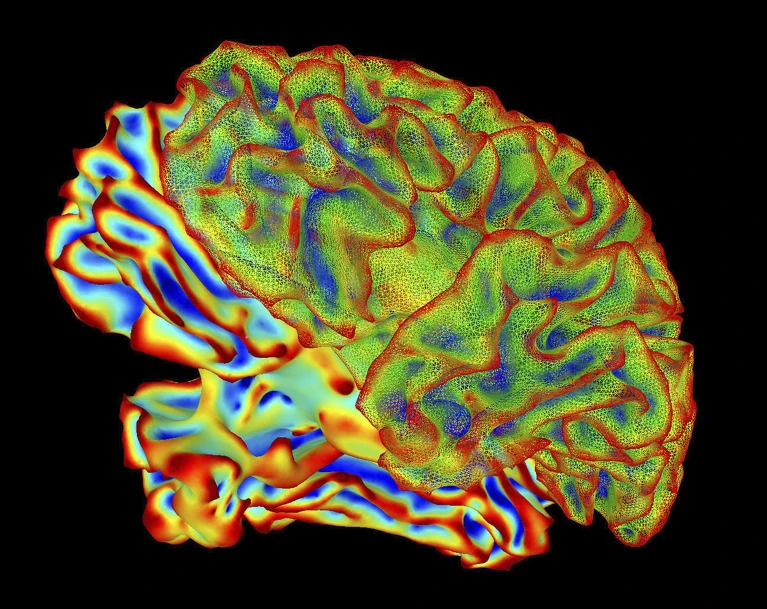

“心智字幕”再現(xiàn)腦中畫面